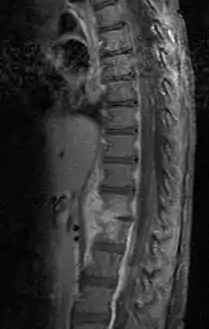

![]() التهاب القرص عند طفل يبلغ عمره سنتين. التهاب القرص عند طفل يبلغ عمره سنتين. | |